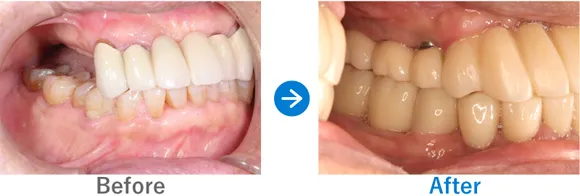

Case2

ブリッジで両隣の歯もダメに…。インプラント治療後は奥歯でしっかり噛めるように!

右下7はかなり前に抜歯後、ブリッジ治療済み。左下6は抜歯後、義歯を入れたがほとんど使っていない

インプラント4本:右下6・7、左下6・7

1,249,500円(内訳:GBR、インプラント4本(ネオデント)、ガイド、仮歯、セデーション、骨補填材、保証20年)

来院の背景

下顎の左右の臼歯部がブリッジによる影響で傷んでしまい、義歯に変更したもののほとんど使えない状態でした。奥歯で噛めないことにストレスを感じ、インプラントを検討。先にインプラント治療をしていた奥様からの紹介で来院されました。

治療結果

来院時の検査で、骨はやせてはいたものの治っている状態だったので、インプラント埋入と同時に骨補填をし、下顎の左右に2本ずつインプラントを埋入し治療完了しました。しっかり噛めるようになり患者様も喜んでおられます。今後はナイトガードを使用して、ブラキシズム(無意識下の歯ぎしり、食いしばりなど)の予防をしていく予定です。